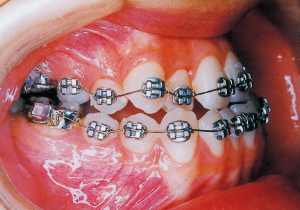

13 5-21-’90 At Phase 2 Treatment

14 6-21-’90 Beginning of second phase

15 3-23-’91 Before surgery

Aware that treatment would be challenging, we proceeded with the first phase of treatment based on the current functional status and anticipated developmental implications (7). During the mixed dentition phase, the body responds readily to treatment, allowing for relatively rapid tooth movement and changes in jaw position (8,9). Subsequently, once freed from mechanical stimulation, growth continues according to inherent predispositions, often appearing to disregard occlusal functional efficiency (10,11). These changes are clearly observable on cephalometric radiographs (12). After confirming the extent and direction of growth, we decided to incorporate surgical intervention into the treatment plan and wait until the age when growth begin to decline.

First Phase treatment: Treatment continued for a long period of 2 years and 5 months, from age 8 years and 6 months to age 10 years and 11 months.

Afterwards, follow-up was conducted, but based on the growth pattern, surgical intervention was determined necessary, and the patient entered a period of regular observation.

Regular Observation: 8 years from 10 years 11 months to 18 years 11 months

Second Phase Treatment:

Pre-surgical orthodontic period: 9 months

Hospitalization period: 2 weeks

Intermaxillary fixation period: Approximately 1 month (orthodontic treatment was not possible during this period).

Post-surgical orthodontic period: 10 months